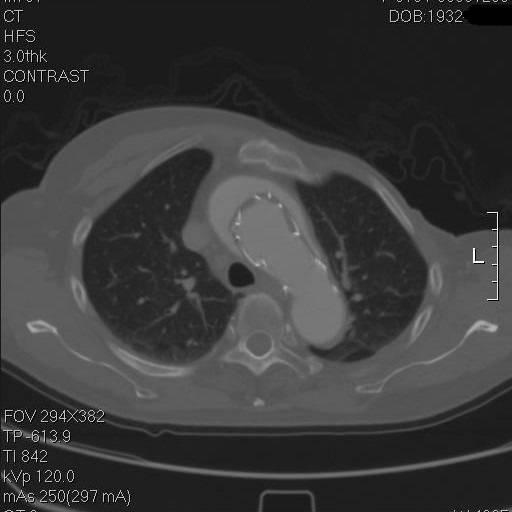

患者是一例A型主动脉夹层,上图中F示假腔,T示真腔,这没什么奇怪。但仔细一看,胸骨的边缘具有高密度影,中间还有一小片低密度区,这例病例接受过前胸正中开胸的手术。

是的,回顾其病史,她一年半前,罹患A型主动脉夹层,第一内膜破裂口在右冠上方,夹层延续到弓部,在弓上分支开口处撕裂形成了出口,她接受了一种显得有些奇怪的术式。